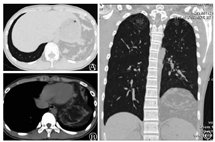

男,15岁。因左下腹疼痛就诊当地医院,胸部CT检查示左侧中下纵隔占位。就诊我院后复查胸部CT检查示:左侧纵隔及左下胸腔见混杂密度团块影,较大界面约13.2 cm×9.7 cm,其内大部呈脂肪密度,伴多发条状软组织密度(图1)。